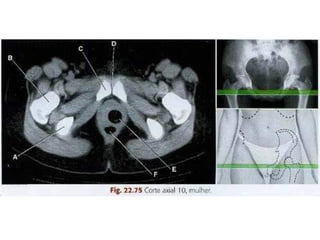

Varredura da Pelve

• Os limites são definidos pela extremidade

superior da crista ilíaca até a extremidade

inferior do ísquio.